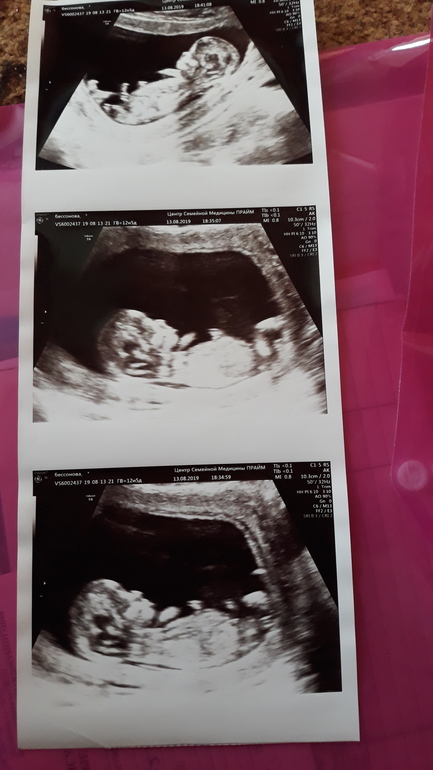

Девченки кто может помочь определить пол,обещают мальчишку а до 2го узи еще месяц ждать.

Ну блин, если на 1м фото половой бугорок а не бедро - то мальчик. Неужели врач не предположил?🤔

на 3й фотографии тоже не понятно что там у него кокички или писюшка🤣